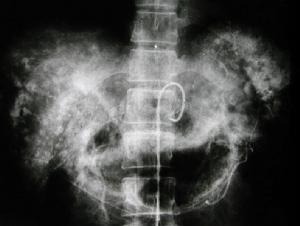

其它輔助檢查: 1.X線檢查 部分患者胸部X線片可示橫膈抬高或其他一些少見徵象,如右側胸腔積液、肺不張或胸膜腫塊。在與膠質二氧化釷有關的血管肉瘤病例中,腹部平片可發現不透光的肝脾和腹腔淋巴結陰影。